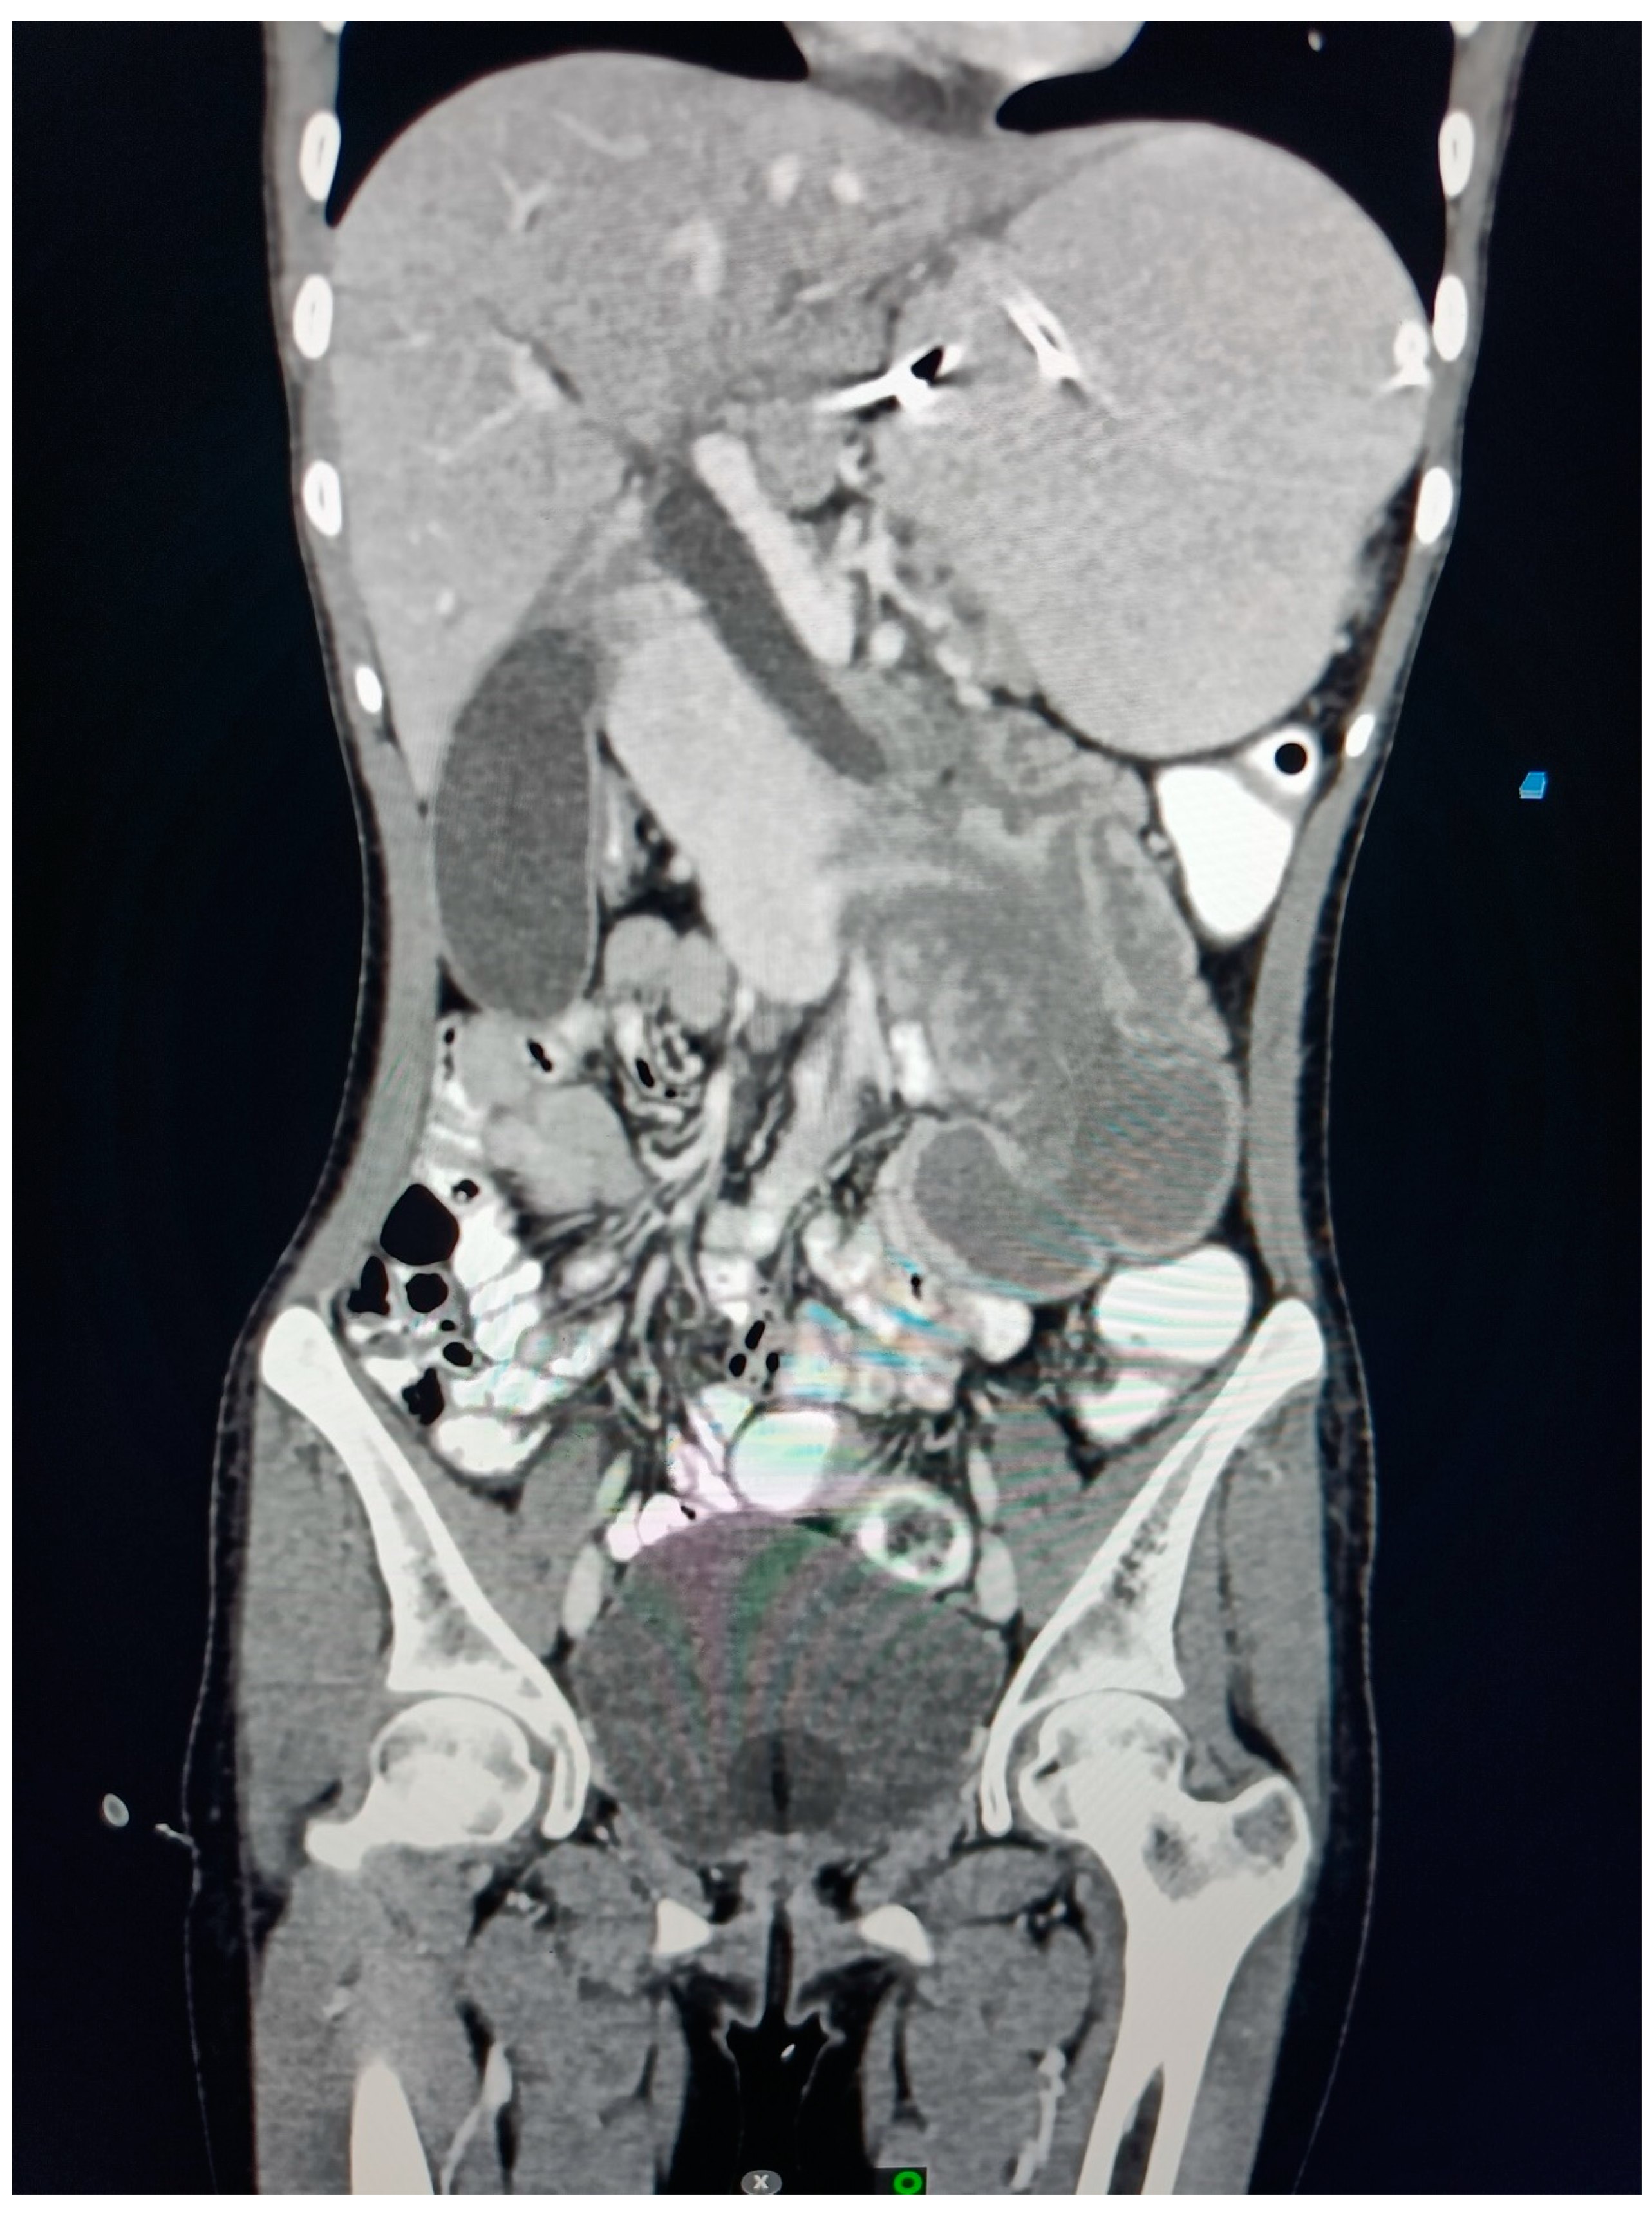

Figure 3. CT Coronal section Abdomen Suggestive of Duodeno-Duodenal Intussusception.

On CECT examination, there is evidence of long segmental intussusception noted at the level of the distal 2nd part of the duodenum with resultant proximal dilated proximal duodenum and stomach. These findings are compatible with the duodenal-duodenal type of enteroenteric intussusception.

The Intussusceptum is 2nd part of the duodenum, the ampulla of the Vater, the head, and the uncinate process of the pancreas while the intussusipens is 3rd and 4th part of the duodenum. The content of the Intussusceptum shows homogenous post-contrast enhancement. The length of the Intussusceptum measures approximately 7 cm.